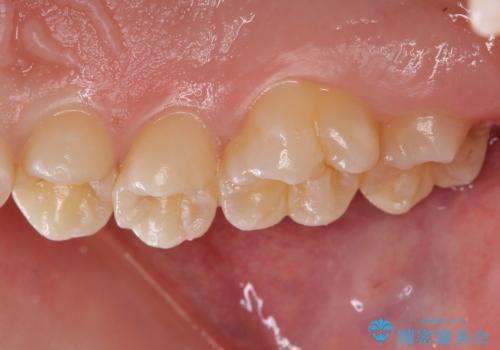

歯と歯の間の虫歯 セラミックインレーでの治療

歯と歯の間は虫歯の好発部位になっています。

外からは確認しにくくても中で大きく虫歯が広がっていることはよくあります。

適合の良い修復物を装着することで今後の虫歯リスクを抑えることができます。